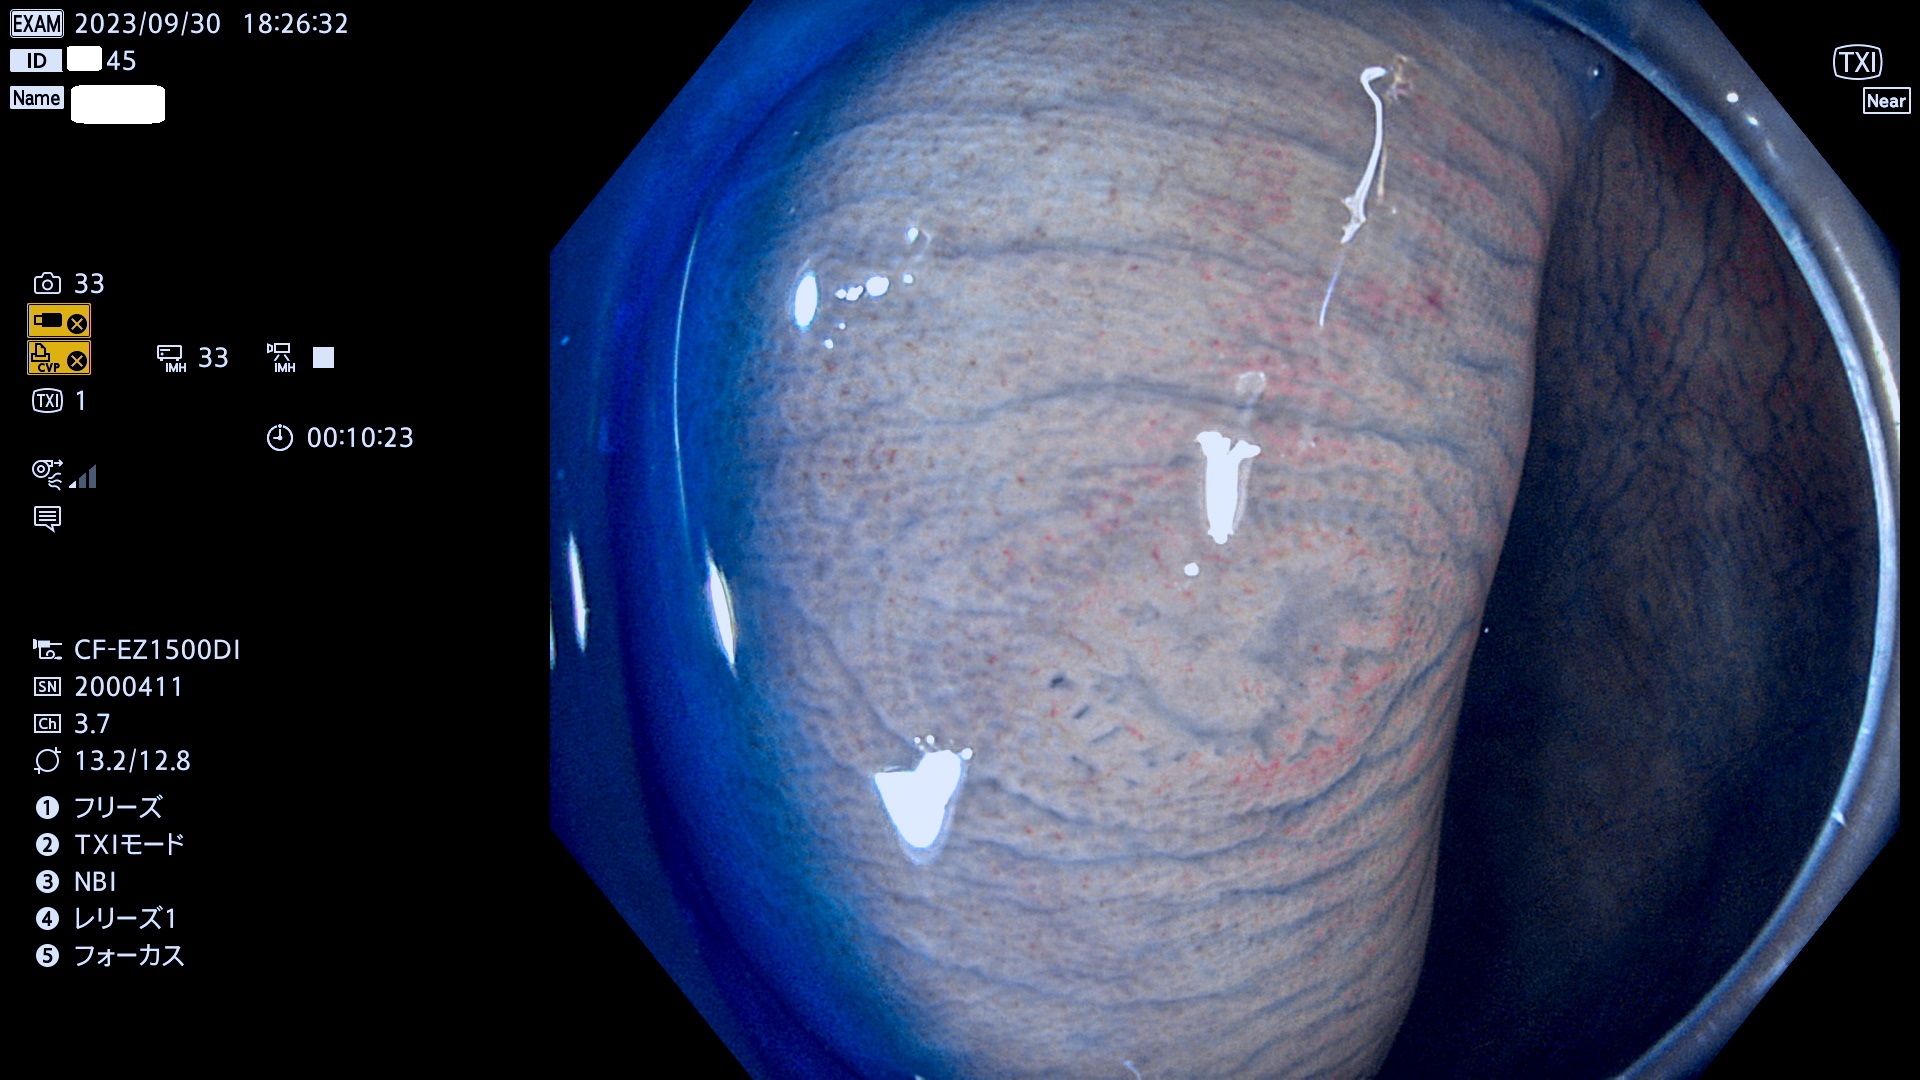

表面型腺腫(Flat Adenoma)の中で、完全に平坦な物をUb、陥凹している物をUcと呼びます。平坦隆起型(Ua)よりも、発見が難しく危険な病変です。このタイプは「内視鏡後・大腸癌の重要犯人」であり、この発見率は「腺腫発見率」よりも、重要な意味があります。

毎週の検査(木・金・土・日)に発見されたUb、Uc型・腺腫を、その週の日曜の夜にUPし1週間、提示します。

抽出の対象期間 2023年9月28日(木)〜10月1(日)の4日間(48件の検査)8件